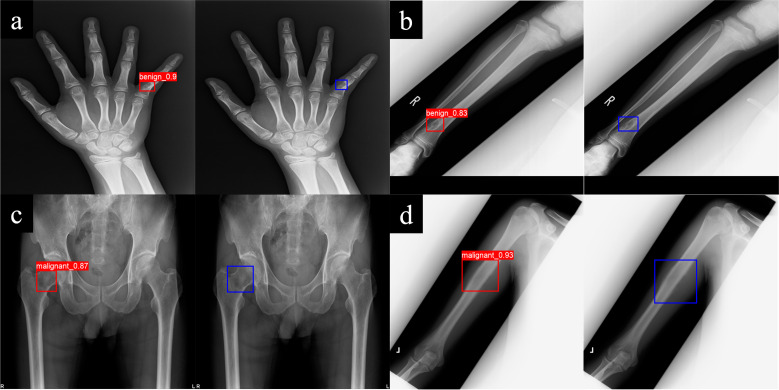

Results: The DINO model achieved a higher mean tumour detection rate (85.7% (95% CI 81.5 to 89.8)) than the YOLO model (80.1% (95% CI 77.2 to 82.9)). For the evaluation of classification performance, we used 113 cases that DINO detected out of 128 randomly selected cases as the evaluation test set. The accuracy and sensitivity of the DINO model, as a superior model, were significantly higher than those of general orthopaedic surgeons. The DINO model correctly classified 78.6% (22 out of 28 cases) of the challenging cases that two or more doctors misclassified. However, DINO's diagnostic errors primarily occurred with tumours that were diagnostically challenging for orthopaedic oncologists or present in unusual sites.